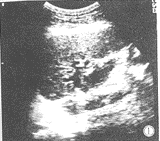

本组病例胆管扩张范围3~18mm(图1);选择穿刺的胆管部位为:右支7人次,右前支12人次,右后支1人次,左外支32人次,左内支2人次。

图1 患者左内叶占位,压迫胆管引起左叶肝内胆管轻度扩张。

门脉矢状段的囊部腹侧胆管扩张3.8mm,其腹侧未见血管结构。